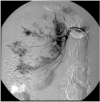

Spontaneous renal hemorrhage (SRH) is a difficult diagnostic problem with various causes. We report a case of SRH and episodic gross hematuria in a patient with metastatic choriocarcinoma involving both kidneys for which successful angioembolization was carried out for control of hemorrhage. There was no evidence of primary uterine tumor and pulmonary or liver involvement. The patient developed gastrointestinal bleeding due to jejunal metastasis while on chemotherapy and surgical resection of the involved segment was carried. However, the patient acquired nosocomial pneumonia and succumbed to sepsis in the postoperative period.